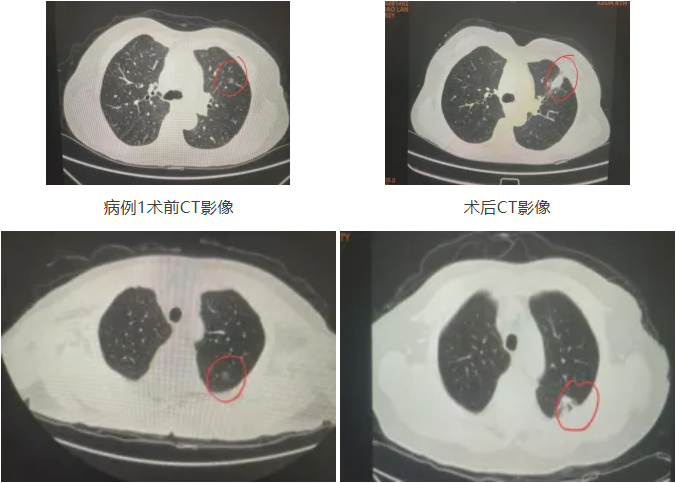

案例一:77岁老大爷,走50米就喘

病情困境:患有慢阻肺、脑梗病史,动脉血气氧分压仅58mmHg,肺功能FEV1 0.85L

不能耐受麻醉及胸腔镜微创手术

家属对于左下肺高危结节(肺早癌)处理意愿强烈

10分钟,完成“精准打击”

经医院多学科(MDT)团队充分讨论为患者制定了微波消融手术方案及周密的围手术期计划。

经充分术前准备后,胸外科高兴才主任团队在CT引导下为患者进行了肺早癌的微波消融手术。从穿刺定位到消融治疗结束,全程不到10分钟。

术中无出血、无气胸

术后呼吸功能未受影响

大爷恢复良好,顺利出院